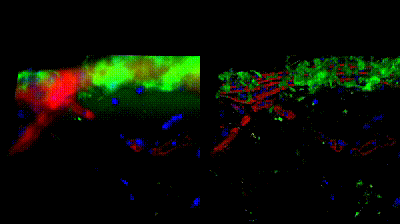

顯示淀粉樣斑塊的海馬體

THUNDER Imager 3D 細胞培養(yǎng)儀

小鼠海馬的縱向腦切片,顯示淀粉樣蛋白斑塊(綠色,用 6E10 抗體染色,抗β淀粉樣蛋白標記物;藍色,DAPI(綠色,用 6E10 抗體染色,抗-β淀粉樣蛋白的標記物),周圍是小膠質細胞/小噬細胞(紅色,用抗-Abi1 抗體染色;藍色,DAPI)。

左圖--原始數據與擴展景深投影;

右圖--大體積Computational Clearing Z 疊加擴展景深投影。

圖片由美國加利福尼亞州 Mehrdad Shamloo 教授提供。